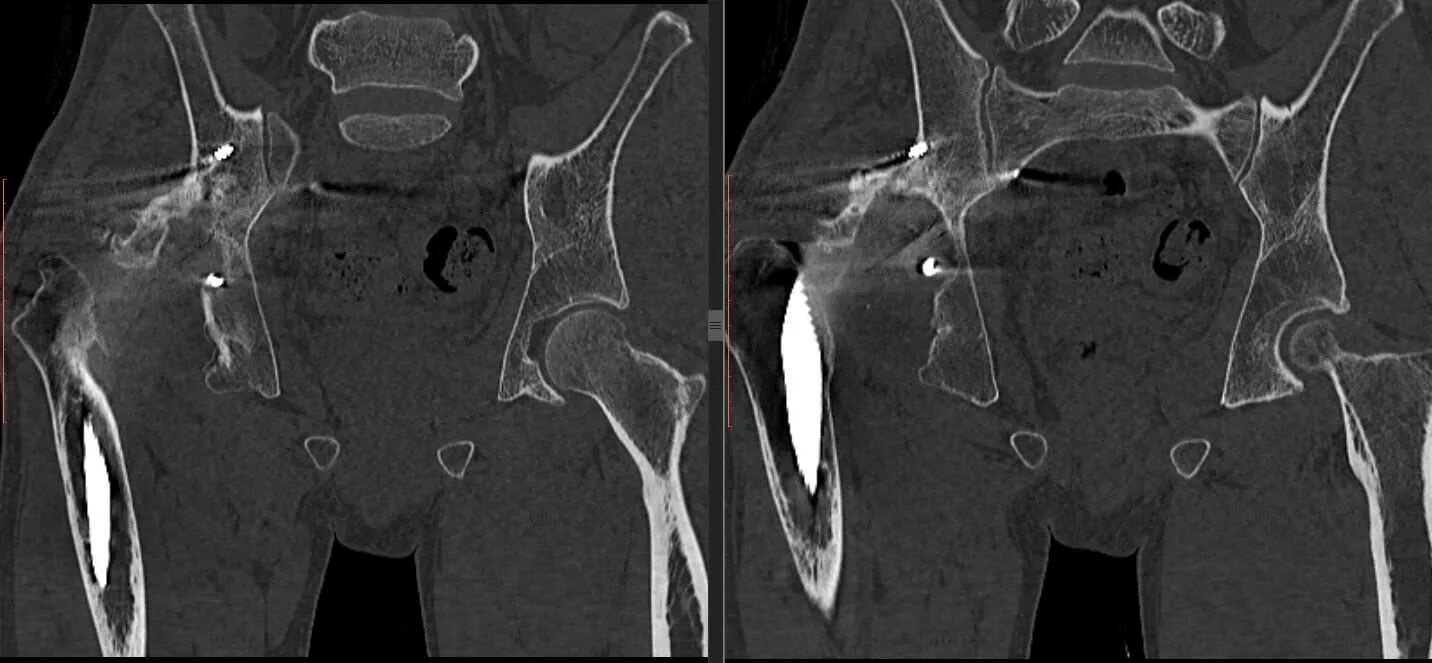

Метастазы в тазу